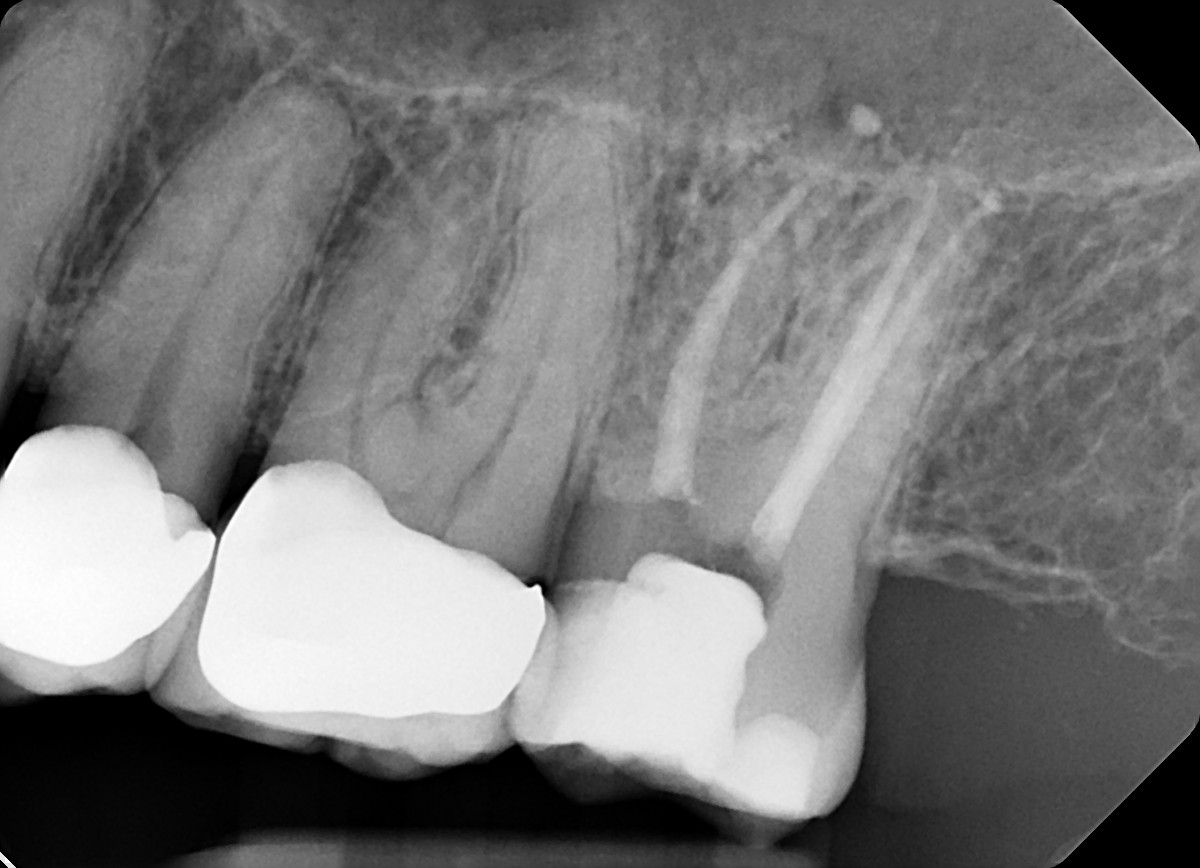

1. What option can explain the crown of the tooth # 1.4?